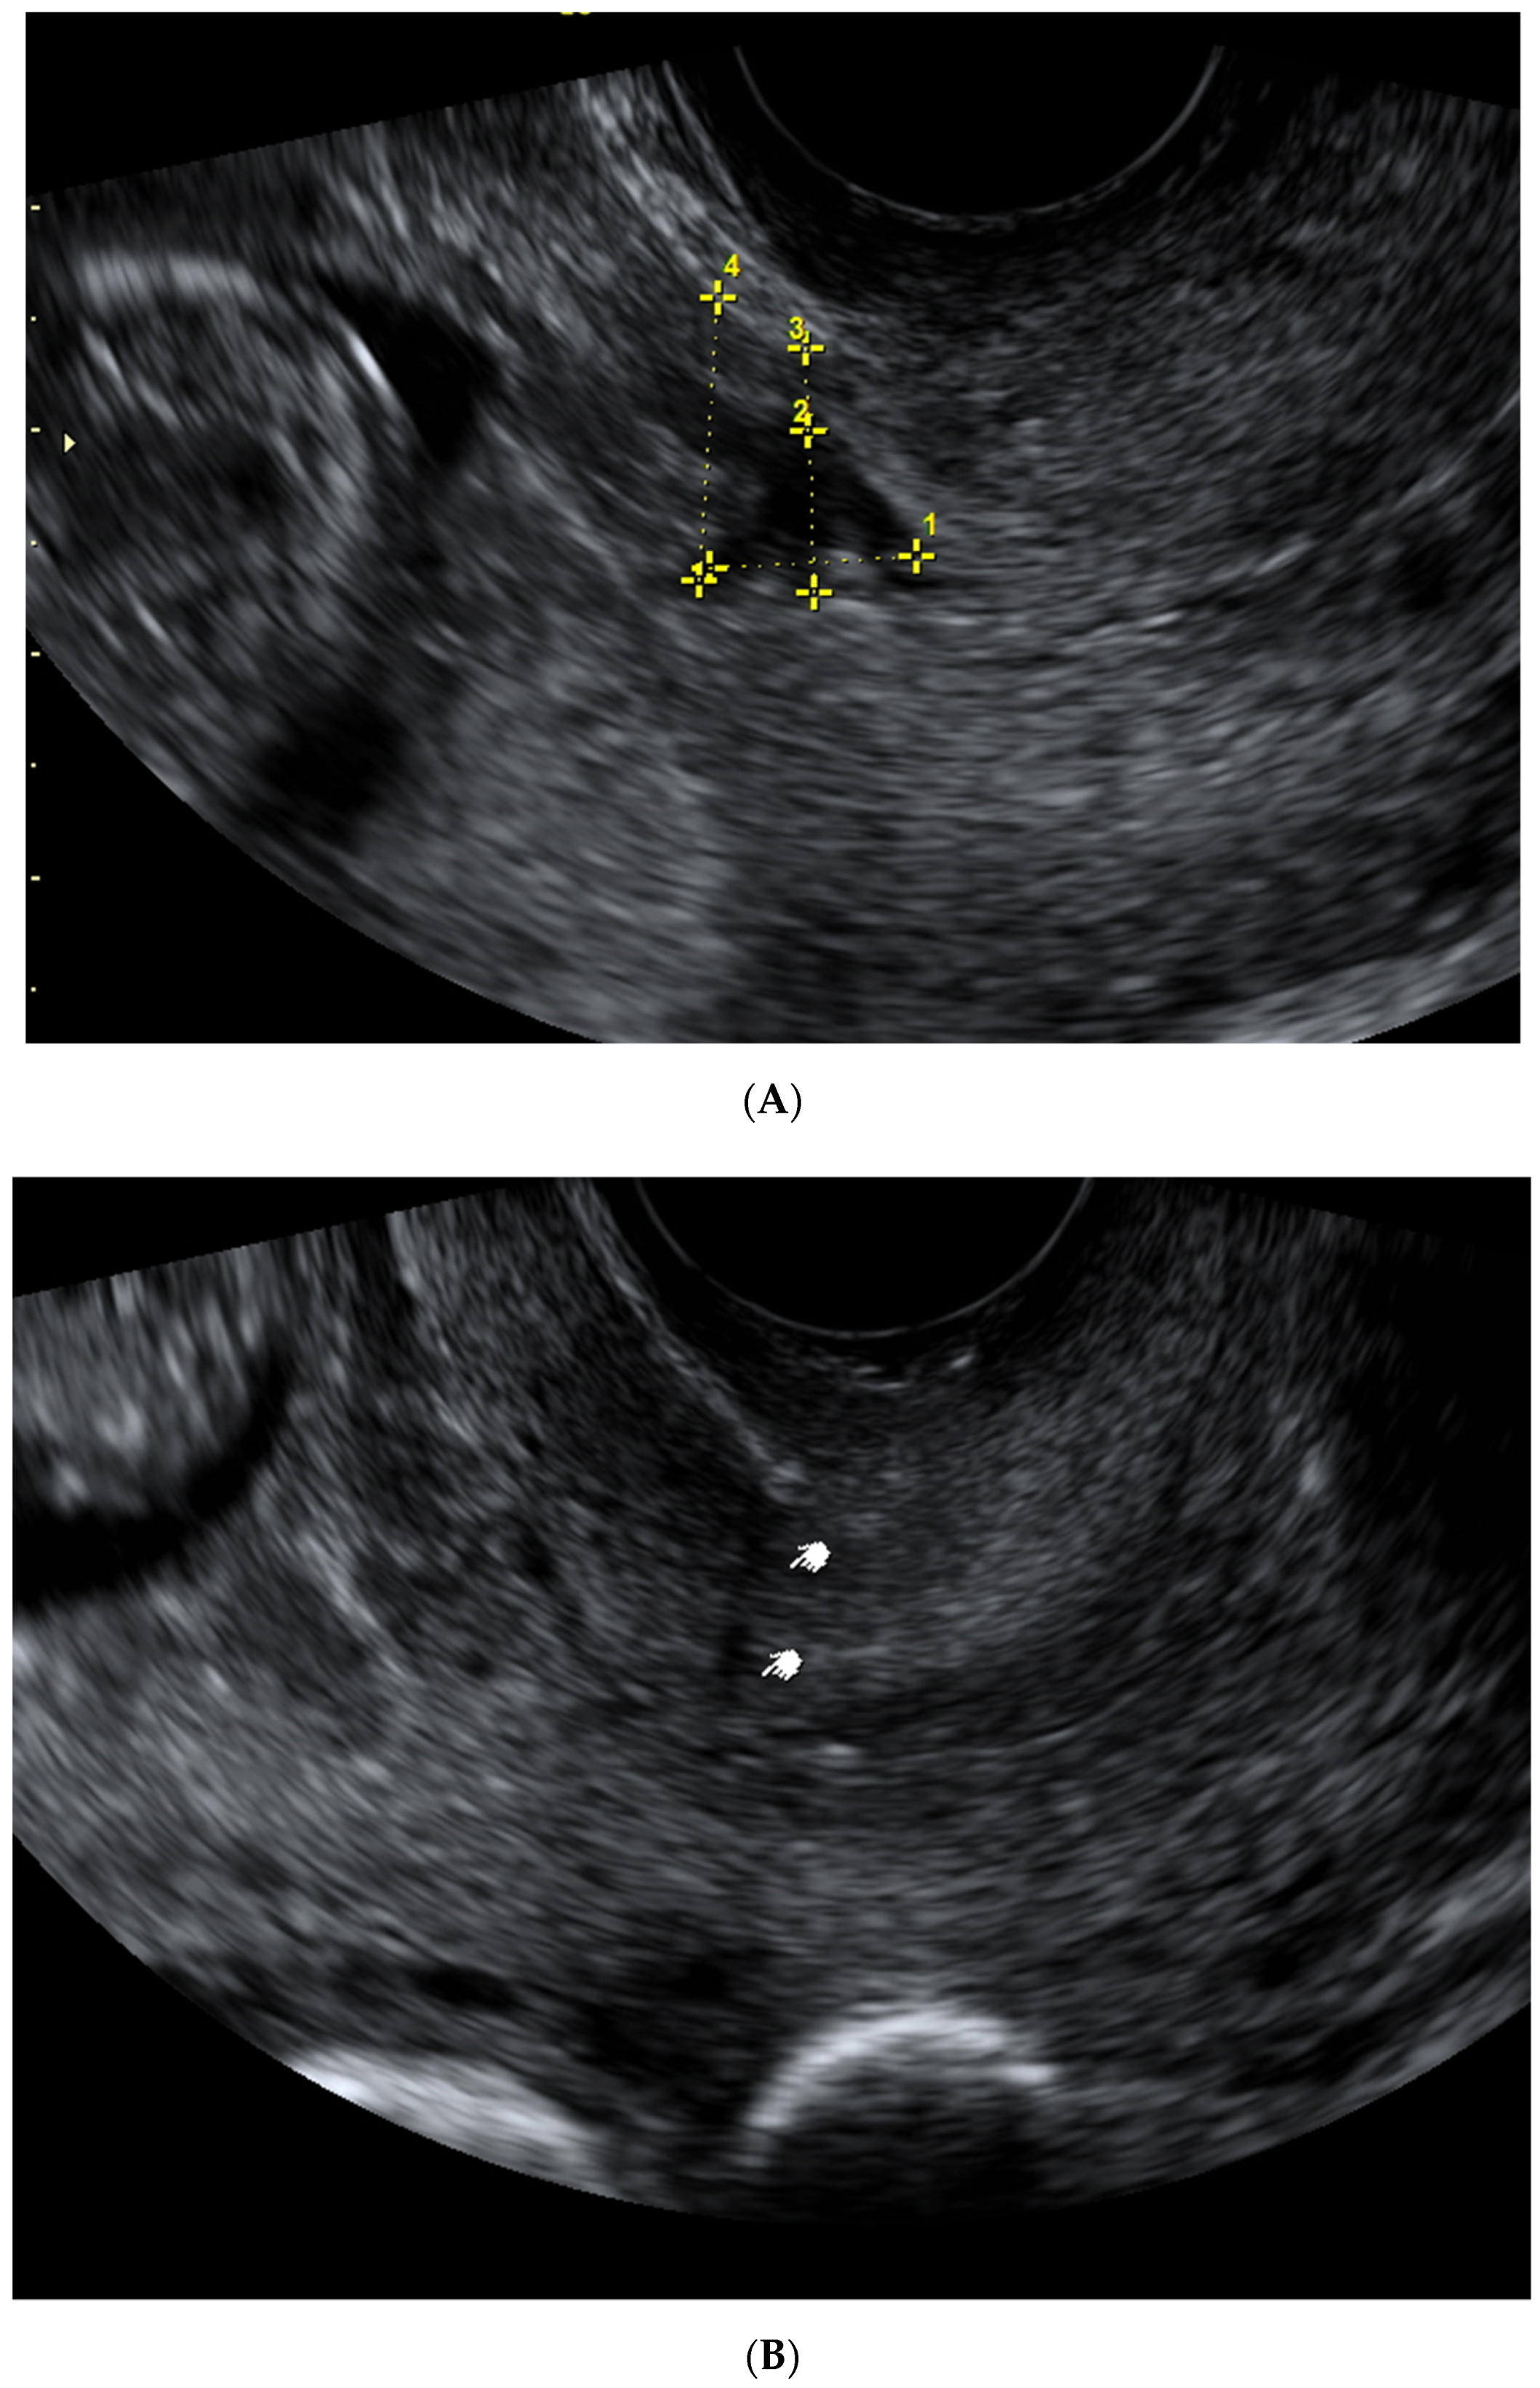

| Scar Characteristic (mm) | First Trimester Median (IQR)  | Second Trimester Median (IQR)  | Third Trimester Median (IQR)  |

|---|---|---|---|

| LUS thickness | - | 6.85 (5.2–9.1) | 4.0 (0.9–5.5) |

| Myometrial thickness | - | 3.85 (2.5–5.3) | 2.1 (1.7–2.7) |